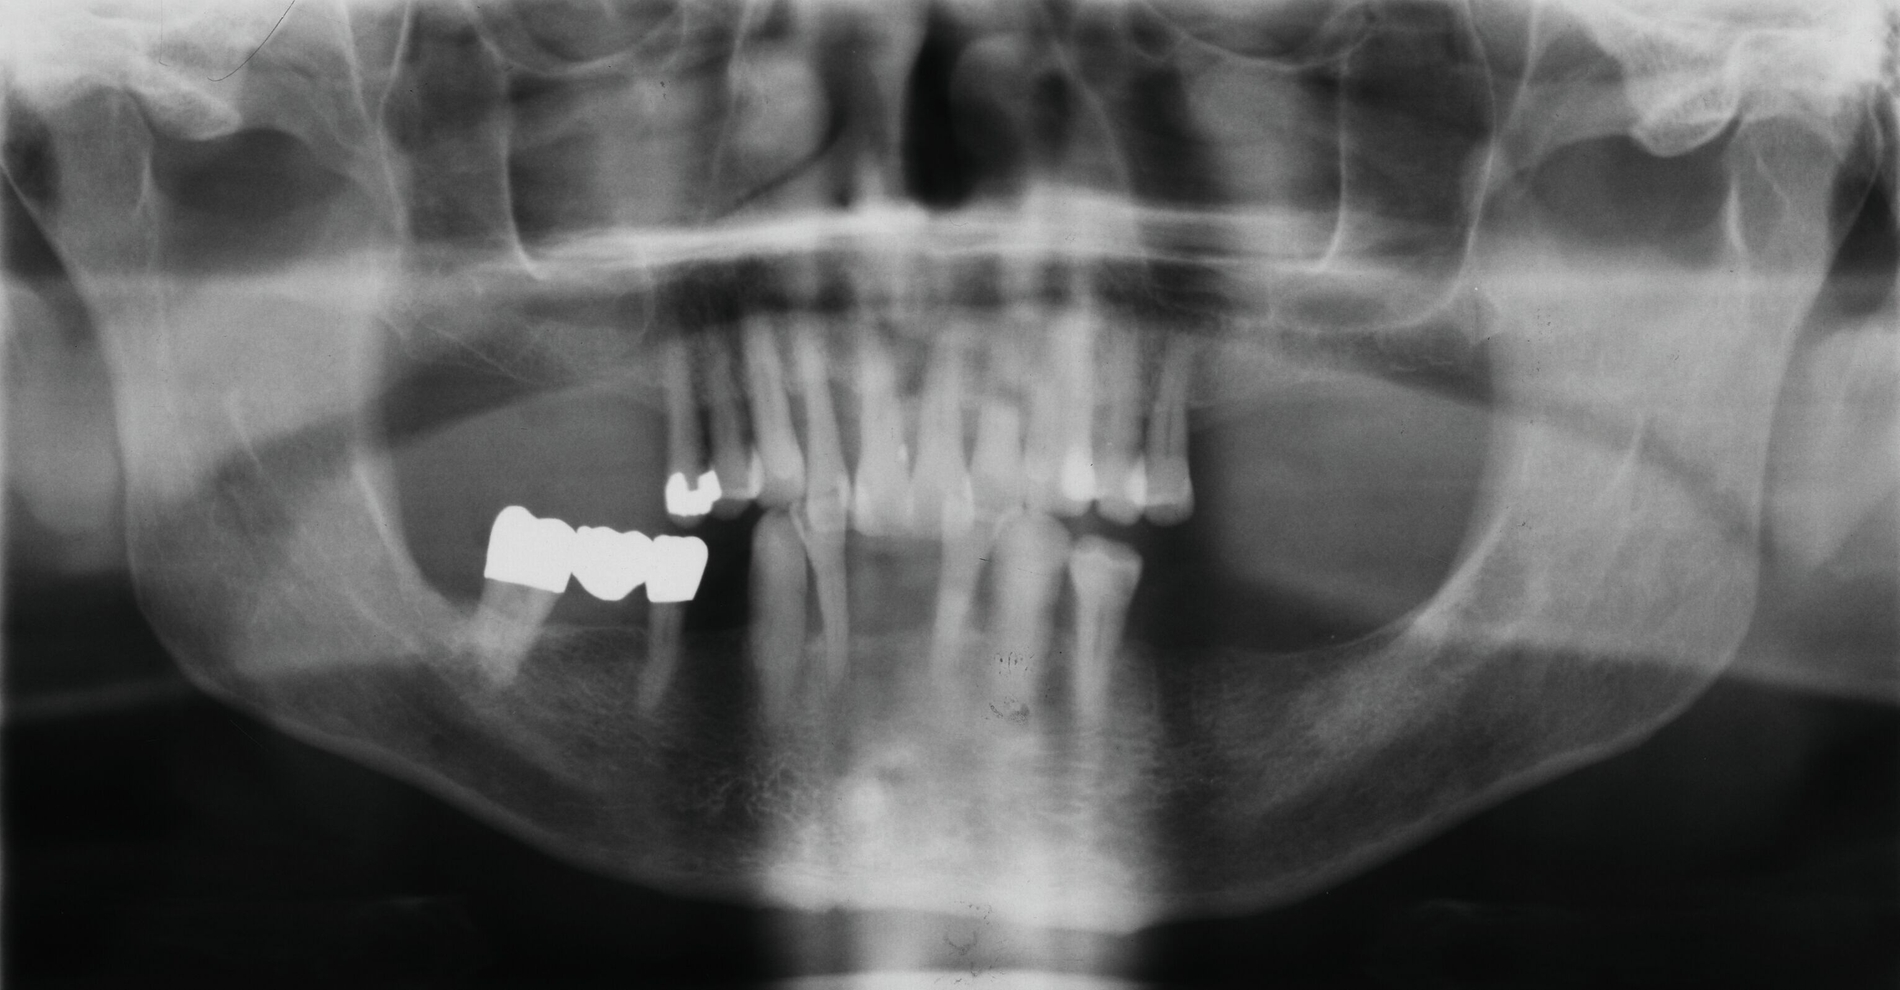

Der Patient wies verkürzte Zahnreihen im Ober- und im Unterkiefer sowie zusätzliche Schaltlücken im Unterkiefer auf (Abbildung 9). Nach Abschluss der ersten beiden Stufen der Therapie (nicht-chirurgische Parodontitistherapie), die darauf abzielte, alle vorhandenen Zähne zu erhalten, wurden an allen Zähnen Sondierungstiefen von maximal vier Millimetern erreicht. Anschließend erfolgte die Planung des definitiven Zahnersatzes im Sinne der aktuellen Leitlinien-Empfehlungen:

Danach wurde der Klinikbesuch für den inzwischen 83-Jährigen zu beschwerlich, und er wurde von einem wohnortnahen Zahnarzt betreut. Die von ihm 19 Jahre nach Eingliederung des Zahnersatzes angefertigte Panoramaschichtaufnahme dokumentiert die unveränderte prothetische Versorgung des Unterkiefers sowie die stabile Situation der verkürzten Zahnreihe im Oberkiefer (Abbildung 16). Für eine detaillierte Darstellung des Fallberichts wird auf die Originalpublikation verwiesen [Wolfart und Kern, 2024].